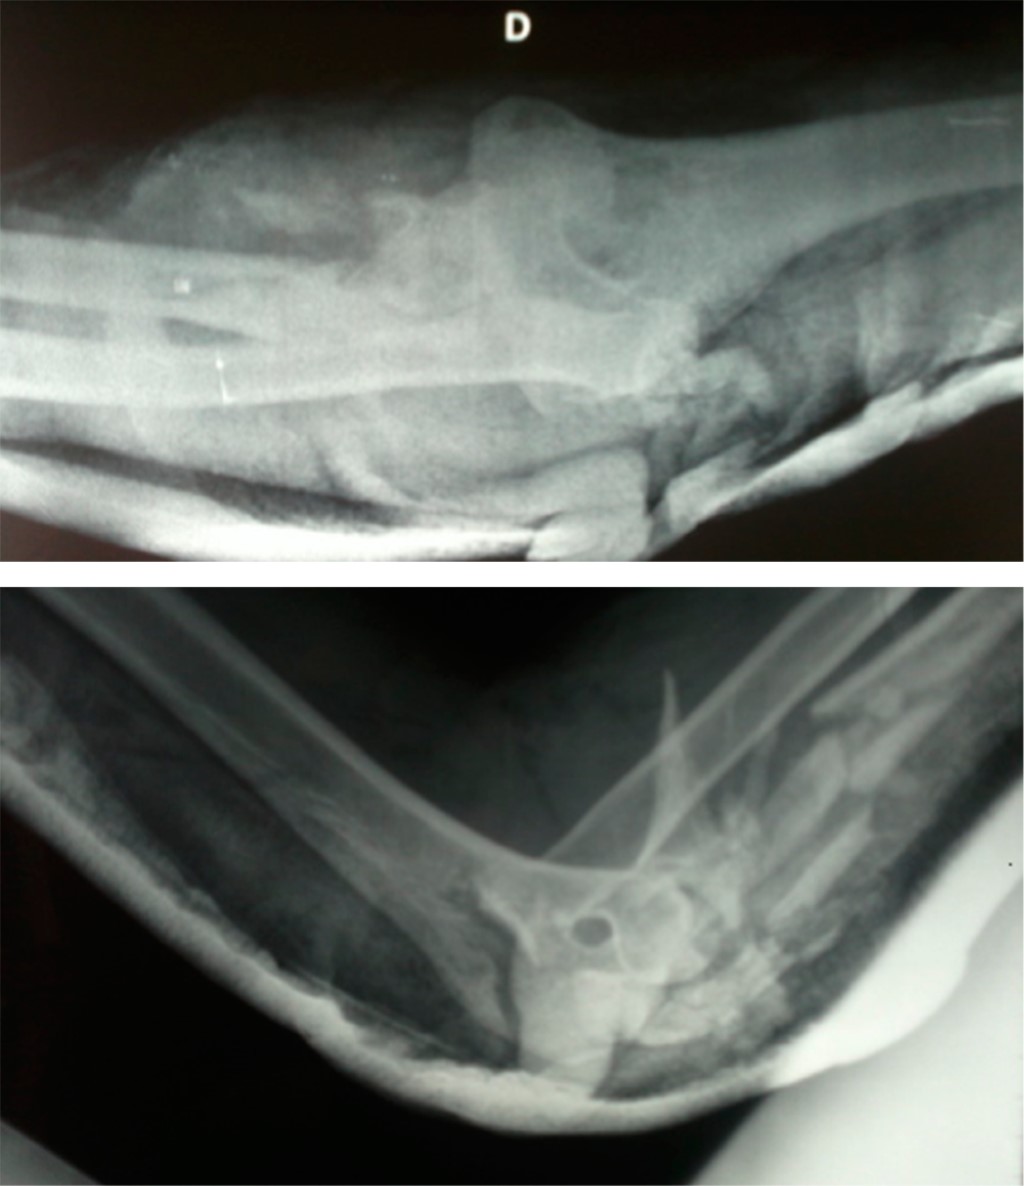

A los dos años postoperatorios, el paciente regresó a la consulta por tener dolor en el codo y grandes defectos de cobertura cutánea con exposición del material de osteosíntesis (Figura 3). Algunos de los tornillos de la placa de cúbito habían sido extraídos por el propio paciente. Se le aconsejó el retiro de la placa, debido al riesgo de infección, pero el paciente se rehusó y no volvió para revisión.

Cuatro años después, el paciente fue ingresado en Urgencias por haber sufrido un nuevo accidente, tuvo una fractura intertrocantérea de la cadera derecha. Además, presentó una exposición completa de 20 cm de largo de la placa del antebrazo, sin signos de infección tras seis años de evolución desde la cirugía (Figura 4A). En la misma intervención, se hizo una fijación interna de la fractura de cadera y extracción de la placa de cúbito. En el antebrazo se observó crecimiento cutáneo por debajo de la placa (Figura 4B).